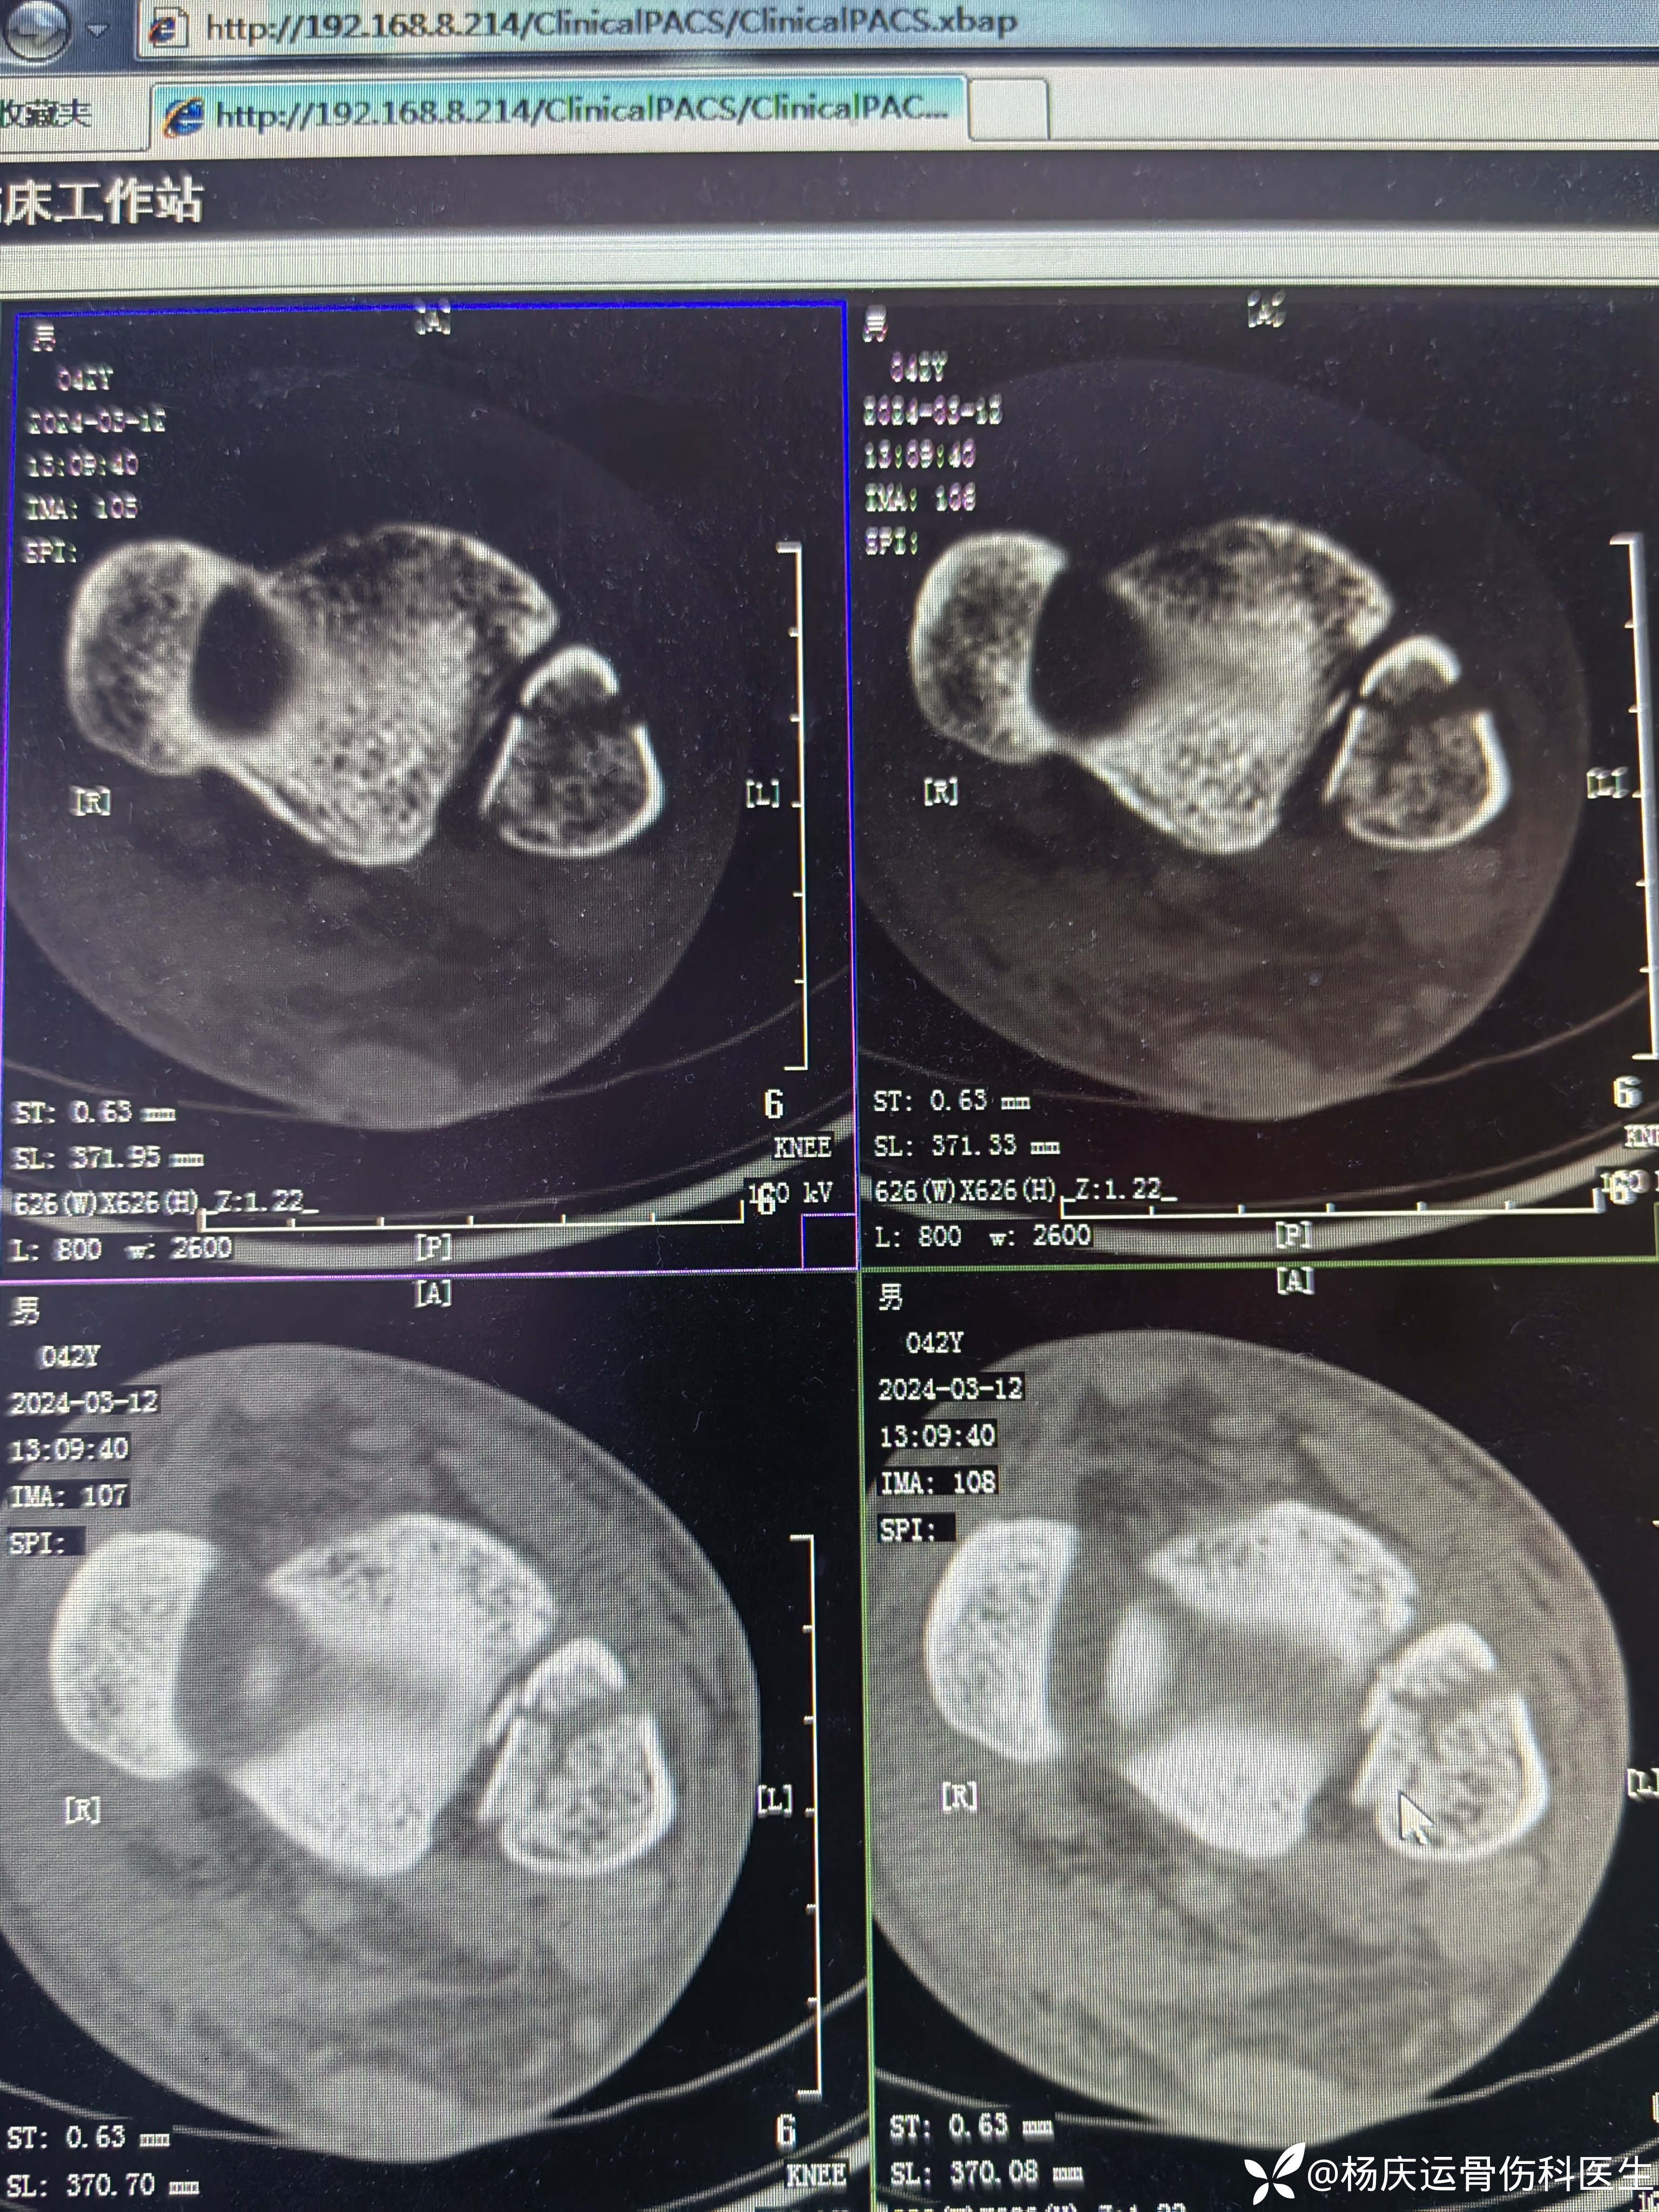

复位前CT